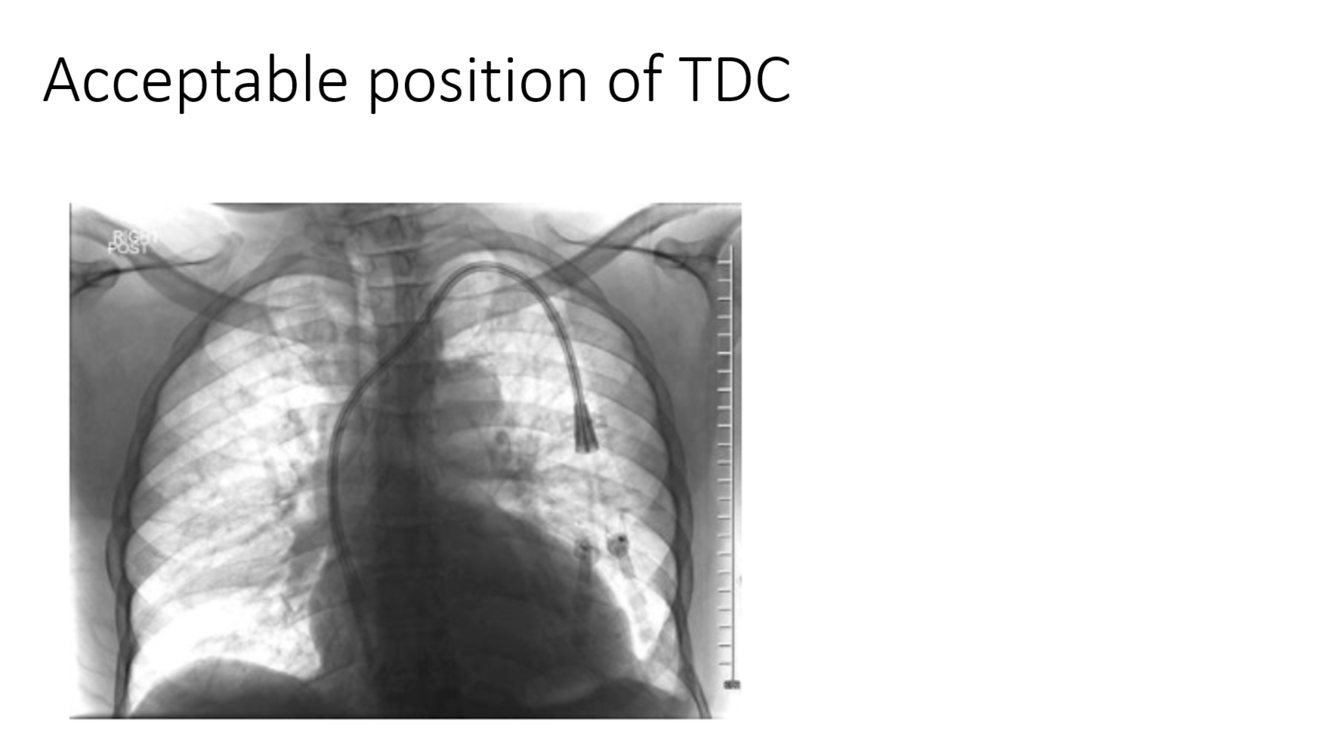

What tool would be the best choice to embolize this pulmonary avm?

vascular plug

Rule 1 of embolics: don’t be dangerous. Clear, large caliber right to left shunt here, so liquids and particles are no good (this is a different scenario than chronic lung disease with bronchial shunting, for which large particles are acceptable). Here, even coils are nerve wracking as they could slip right through, though are definitely an acceptable answer. The vascular plugs are a nice option here as migration risks are lower.